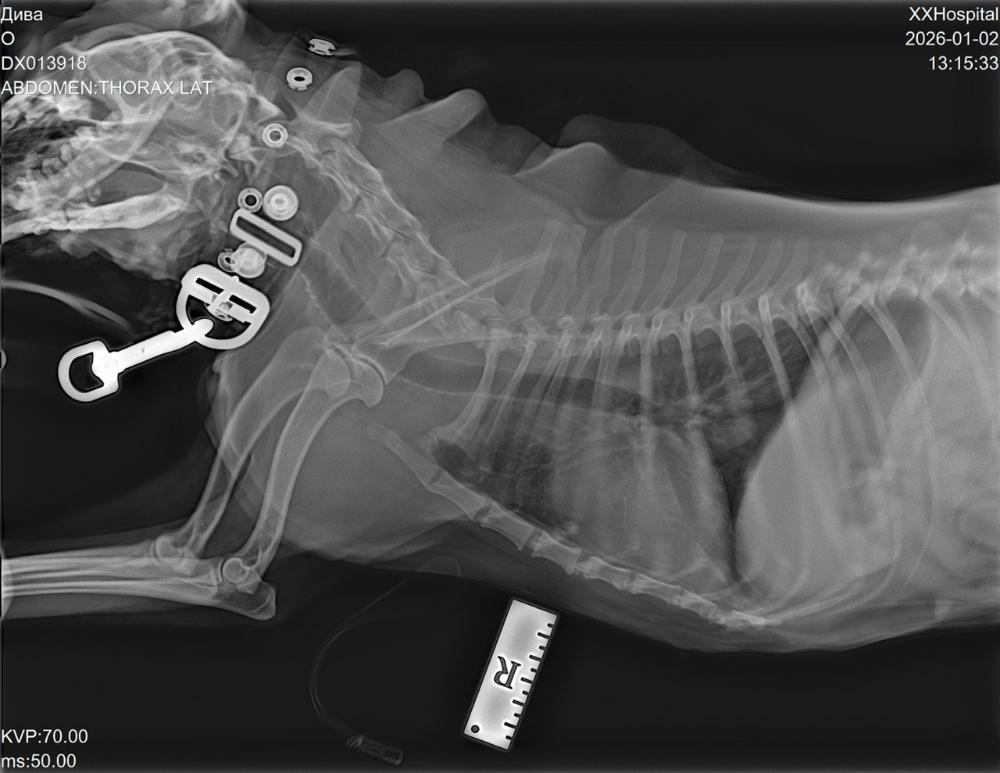

С'ездили мы сегодня к врачу, сделали кардио обследование, рентген, дополнительный анализ ( ждём всё на почту).

По сердцу всё в пределах возраста, сделали рентген - затемнение в лёгких, сдали дополнительные анализы ( по результатам либо надо будет делать КТ, либо бронхоскопию).

Кардиолог, рентген, анализы - 9339р.

Зоотакси -1330р.

Остаток: минус 6519р.